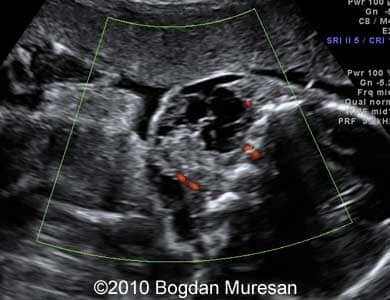

Images 5,6: Image 5 shows a low vascularization of the tumor. Image 6 shows a transverse view of the tumor which is located bilaterally at the level of the mouth.

Lymphangioma_Muresan_6